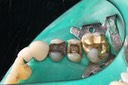

Matt Dodson #3 prep